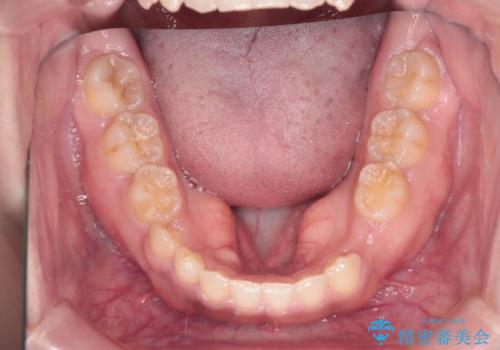

- 後続永久歯が欠損した患者様です。

矯正治療にて歯並びを改善したのち、インプラントにて咬合回復を行う治療計画としました。

捻転が強い部分だけはワイヤーの部分矯正で対応しております。